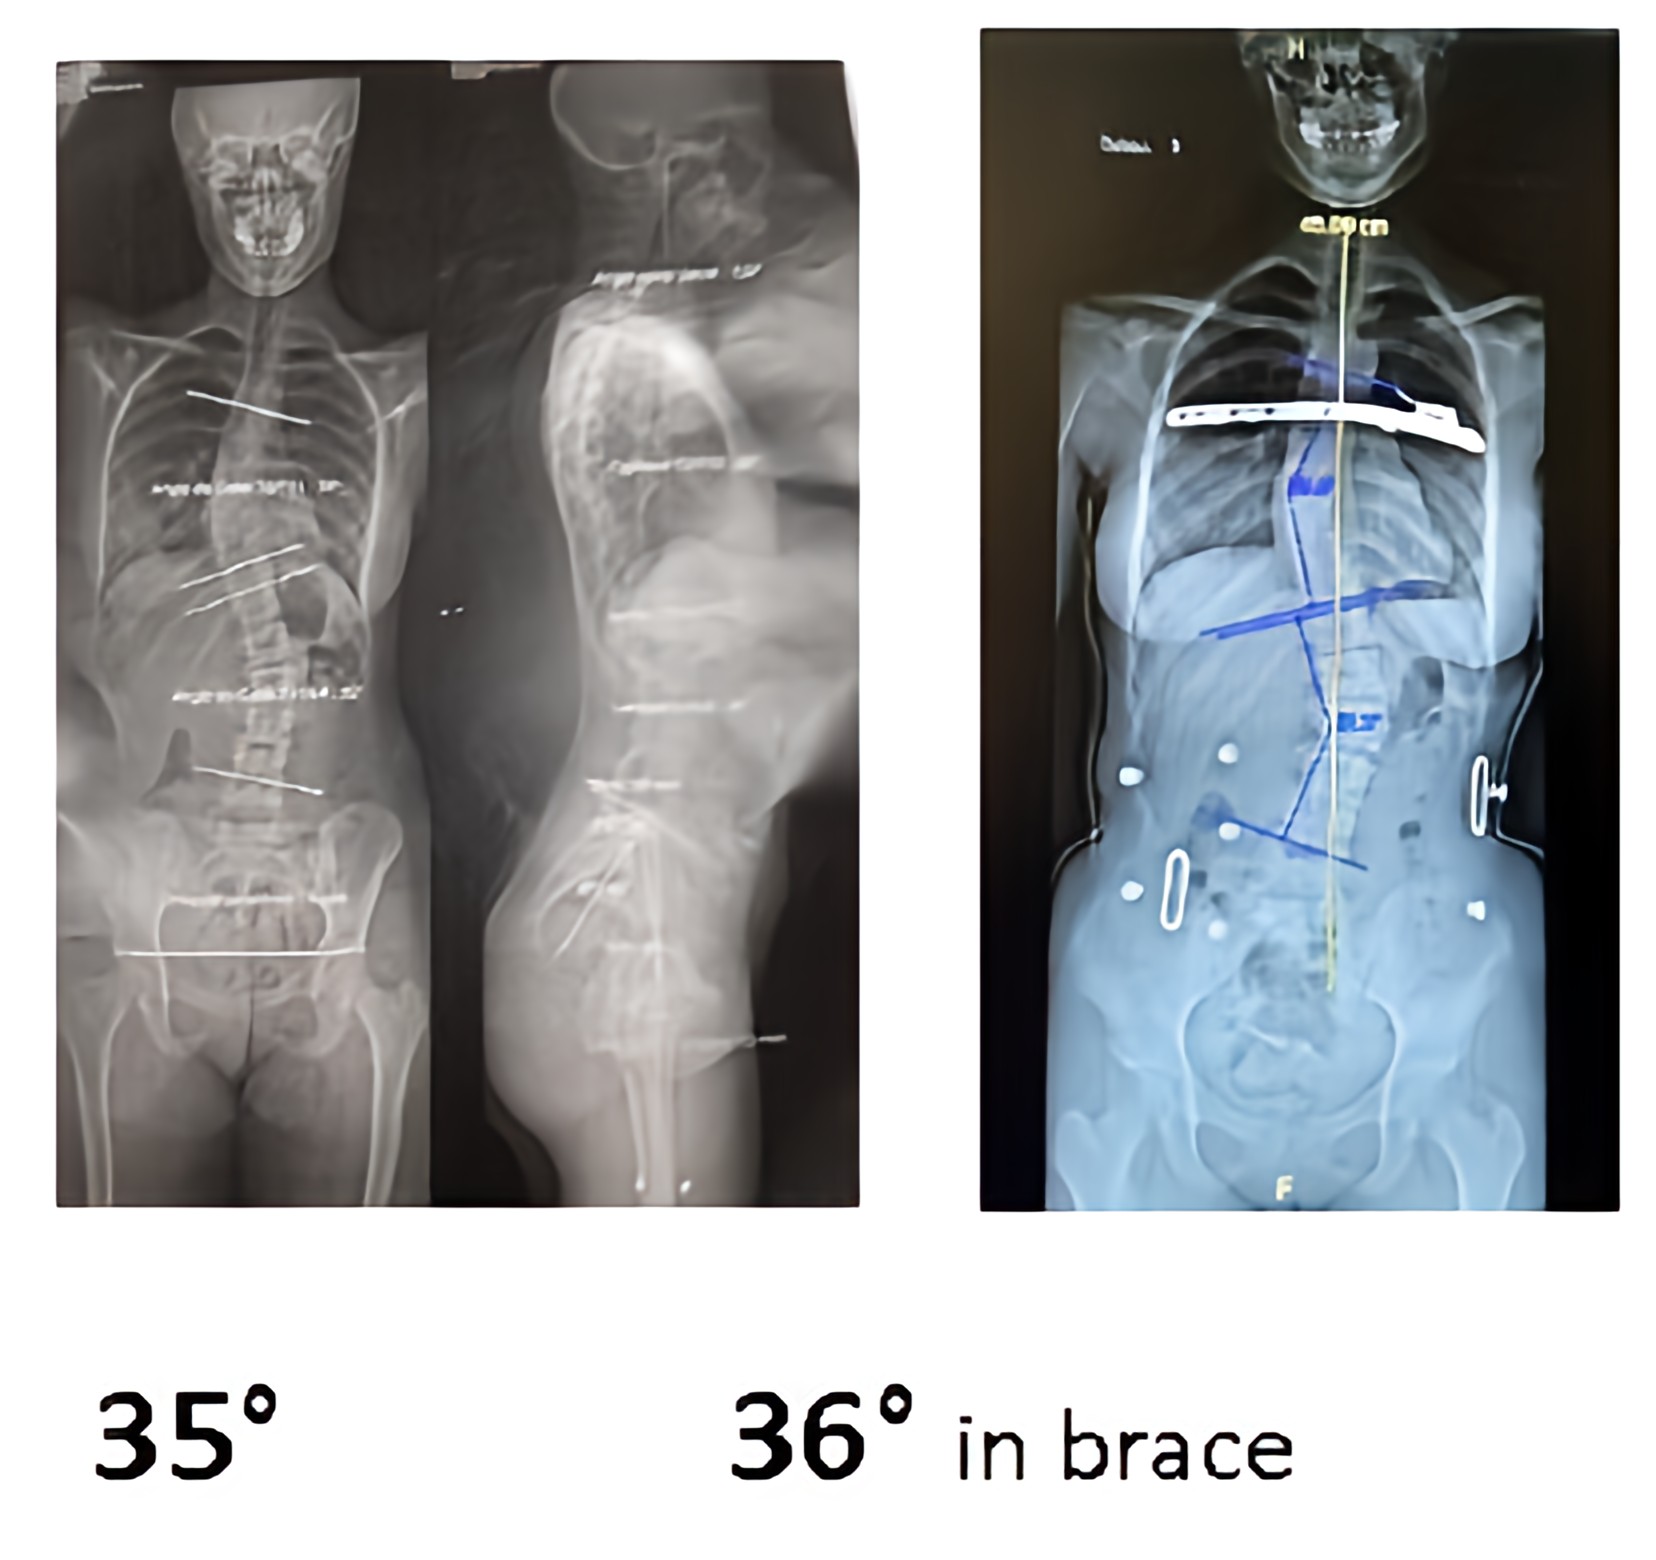

Cobb angle is today unsuitable and outdated. The “top view” will be a better tool in the future.

Do we have to validate and pay for this useless work ?

Or this one, increasing flat back ?